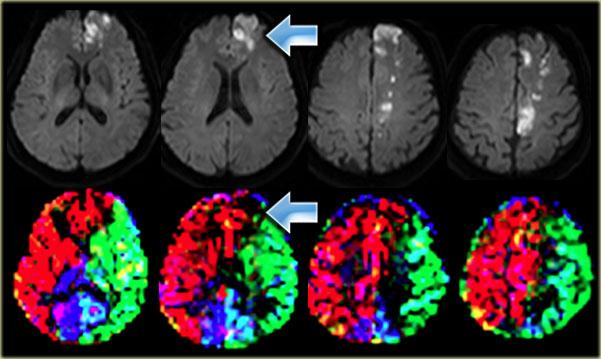

Bên trái là ba lát cắt CT liên tiếp của bệnh nhân tắc động mạch cảnh trong phải.

Tình trạng giảm tưới máu bán cầu phải dẫn đến nhiều ổ nhồi máu vùng ranh giới sâu.

Hình thái nhồi máu vùng ranh giới sâu này khá phổ biến và cần thôi thúc người đọc tiến hành khảo sát các động mạch cảnh.

Bên trái là hình ảnh của bệnh nhân có các ổ nhồi máu nhỏ ở bán cầu phải tại vùng ranh giới sâu (đầu mũi tên màu xanh lam) và tại vùng ranh giới vỏ não giữa lãnh thổ ĐM não giữa (MCA) và ĐM não sau (PCA) (mũi tên màu vàng).

Có bất thường tín hiệu tại động mạch cảnh phải (mũi tên màu đỏ) do hậu quả của tắc mạch.

Ở những bệnh nhân có các bất thường gợi ý nhồi máu vùng ranh giới, cần luôn khảo sát hình ảnh động mạch cảnh để tìm kiếm bất thường tín hiệu.

Bên trái là một ví dụ khác về các ổ nhồi máu nhỏ tại vùng ranh giới sâu và vùng ranh giới vỏ não giữa lãnh thổ ĐM não giữa (MCA) và ĐM não sau (PCA) ở bán cầu trái.

Bên trái là ví dụ về nhồi máu tại vùng ranh giới sâu và vùng ranh giới vỏ não giữa lãnh thổ ĐM não trước (ACA) và ĐM não giữa (MCA).

Bất thường cường độ tín hiệu tại động mạch cảnh phải là hậu quả của tắc mạch.

Sự kết hợp các dấu hiệu này rất phổ biến đến mức một khi đã nhận biết được hình thái, bạn sẽ gặp lại nhiều lần.